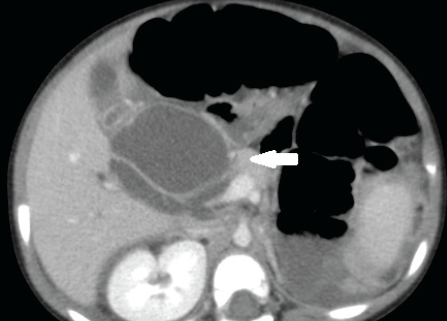

Lauren Astrug, MD; Michael Baldovsky, DO; Daniel A. Thimann, MD

A 2-year-old girl, born at 30 weeks’ gestation with chronic lung disease, presented to the emergency department (ED) with concerns for constipation. She had been having ball-like stools for the past month. ...